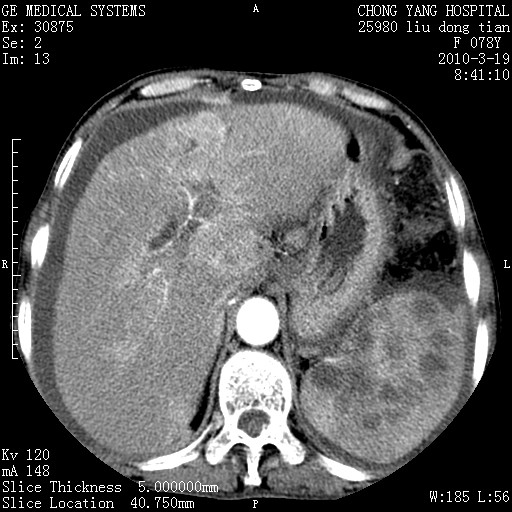

标题: CT25199:F 78Y 腹胀半年 消瘦乏力 [打印本页]

胆囊壁增厚并明显强化,胆囊癌伴多发转移瘤可能性大,淋巴瘤不除外,右肾囊肿,胸腹水.

考虑nhl,肝、脾、腹膜腔及腹膜后多发淋巴结受侵,腹水,右肾囊肿,慢性胆囊炎,右侧少量胸腔积液。

胆囊有软组织影有强化,支持胆囊癌,肝脾、腹膜后淋巴结转移。

nhl的淋巴结多围绕主动脉,而且主动脉会移位,所以不考虑nhl。

分开来讲:肝左叶、尾叶病灶有不均强化像肝癌;

脾脏病灶无强化,像多发囊肿或淋巴管瘤,不除外淋巴瘤(低强化);

胆囊增生性病变:胆囊癌,腺肌增生症,慢性胆囊炎;

肝门、胰腺头、腹膜后多个团块: 淋巴瘤,转移;

腔静脉肝内段细小有无布加可能?

一元论最好了 淋巴瘤所致改变; 胆囊癌转移不像,胆囊周围肝组织清晰,肝癌淋巴结转移?三元论都不止。

最后报的胰头癌多发转移,脾脏单独考虑囊肿或淋巴管瘤。